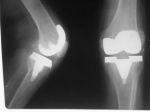

置换关节引起的关节感染可致置换处松动,失效和脓肿.有较高的发病率和病死率.在术后1年内发病的,多有术后伤口感染持续数月才愈,修复关节在休息或承重时出现疼痛.近1/3的手术患者在1年以后出现关节感染,多由关节外感染源引起菌血症所致(如肺炎,UTI,皮肤感染,牙周炎,器械伤).25%的患者有关节痛发作,2周内有摔跤史,20%的患者有手术史.患者可能无发热或白细胞增多,但血沉加快.